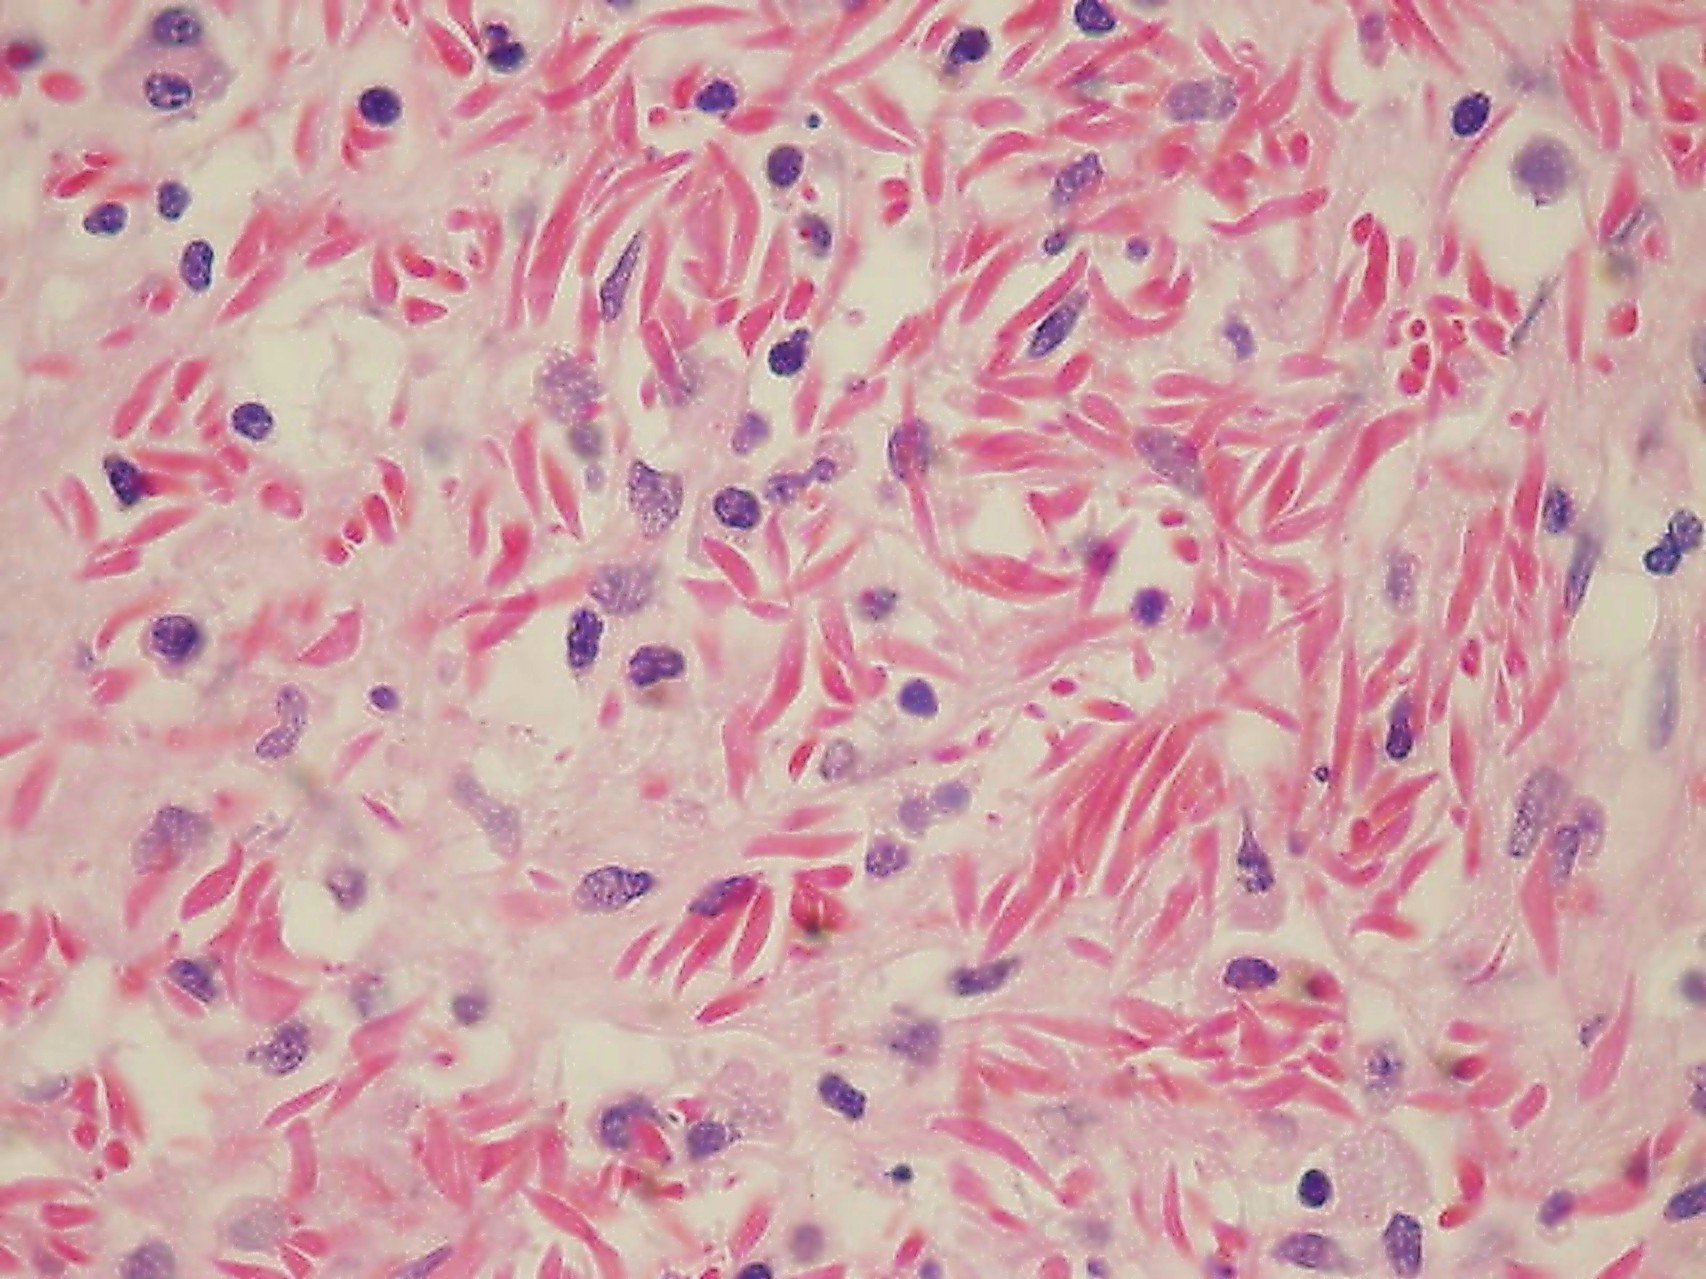

Patología Molecular

El diagnóstico sobre muestras de tejidos y líquidos corporales en plena era de la medicina del futuro, está basado en la integración de técnicas y conocimientos diferentes.

Hoy más que nunca es importante integrar una buena historia clínica con un correcto estudio de imagen y una buena morfología que además puede estar apoyada con proceso especiales complementarios relacionados con la Inmunología, Biología Molecular y Citogenética, generando así un estudio integral conocido como Patología Molecular.